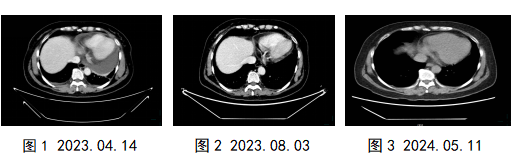

1年多前,蔡女士出现胸闷,活动后气促,癌胚抗原(CEA)稍高于正常。2023年4月,蔡女士来我院复查胸部CT显示:心包见大量积液(最深处3.9cm),穿刺(心包积液)见癌细胞(图1),诊断为宫颈癌多程治疗后心包转移。陈文娟主诊团队对蔡女士进行心包置管引流+局部靶向药物+化疗灌注。经治疗,蔡女士心包积液消退,胸闷气促症状缓解,复查胸部CT(图2)显示心包积液消失,肿瘤标志物恢复正常。近一年来复查影像未见复发,且肿瘤标志物检查均正常(图3)。